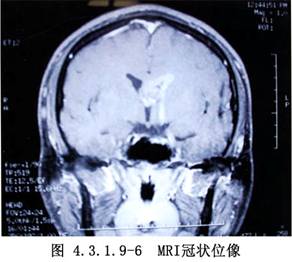

側腦室內腫瘤的發生率較低,據國內外文獻報道約佔顱內腫瘤總數的0.75%~2.8%。在側腦室前部和體部者,多爲室管膜瘤,在三角部、顳角和枕角區者,多爲乳頭狀瘤或腦膜瘤。側腦室周圍、丘腦和腦室室管膜下生長的膠質瘤,也可長入腦室內。其他如上皮樣囊腫或皮樣囊腫等也偶可見到。側腦室內腦膜瘤約佔顱內腦膜瘤的2.5%~6.3%,以女性較多,年齡多在30歲左右,且好發於左側側腦室。室管膜瘤則以嬰幼兒和學齡前兒童多見(圖4.3.1.9-1~4.3.1.9-6)。

頸動脈造影顯示脈絡膜前動脈增粗,椎動脈造影顯示脈絡膜後動脈增粗、走行異常和腫瘤染色等,都是確診側腦室腫瘤的有力依據。自CT、MRI問世以來,確診已較簡易、安全。由於手術經驗的積累,療效亦不斷提高,大多能全切治癒。